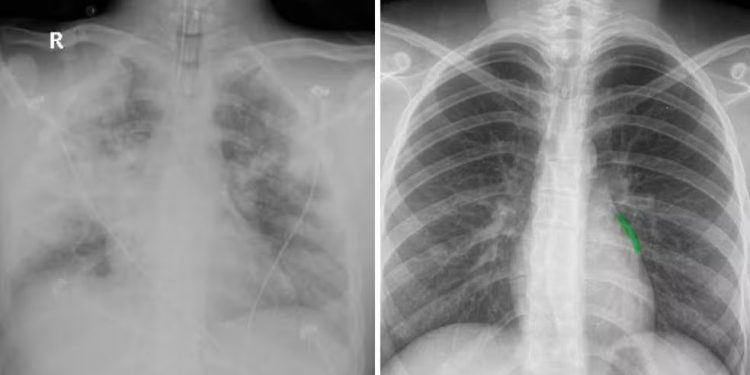

Do lado esquerdo, imagem do pulmão de Diego todo comprometido. Do lado direito, a imagem de um pulmão saudável. — Foto: Divulgação

Ela usou a imagem de um pulmão saudável (acima, esquerda, com tons mais escuros) para comparar com o pulmão do filho (acima, na direita, imagem esbranquiçada). “Ele nem pulmão tinha de tanta infecção”.